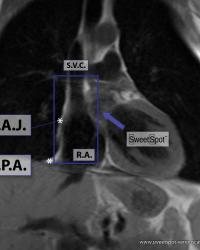

Figure - 02

Cardiac anatomy conduction pathways |